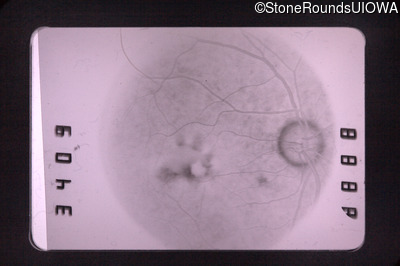

Fundus Photography - Right - 20/70

Exemplar